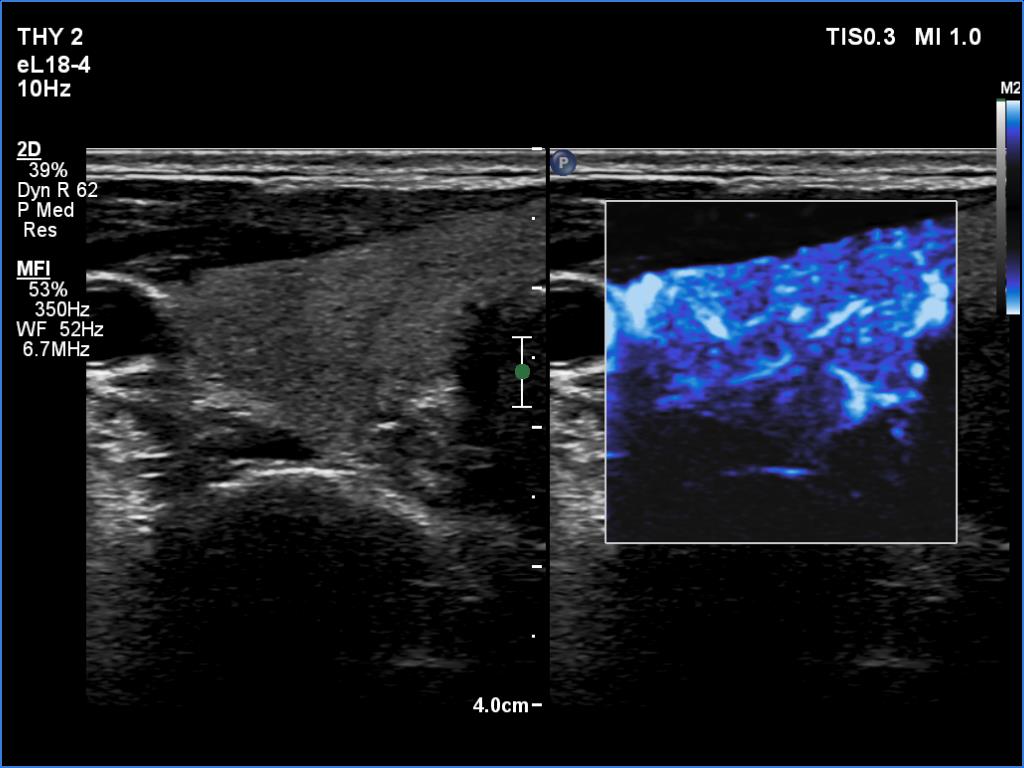

Right lobe, longitudinal scan

Right lobe, transverse scan, microflow imaging. The vascularity is not increased.